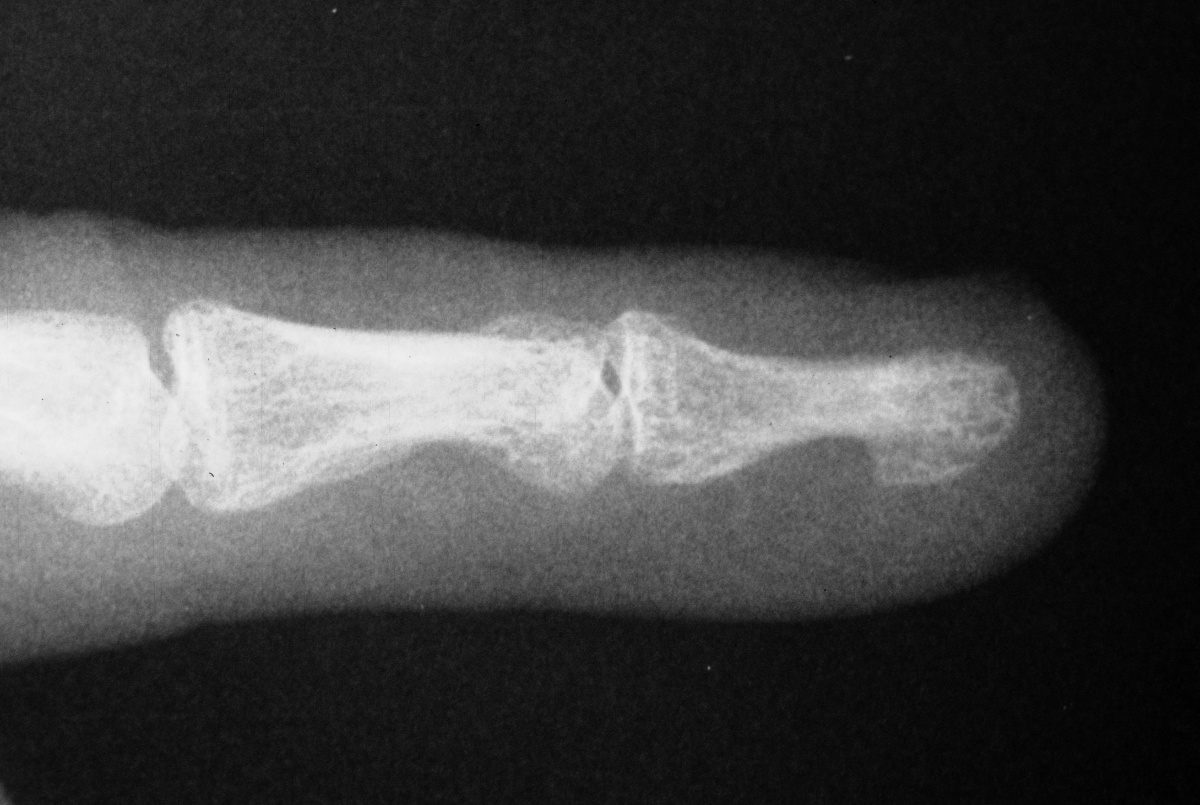

| The distal nail

plate fragment was removed, and the fracture was

stabilized with K-wires as in case 1. |

| Two months

following hardware removal. |